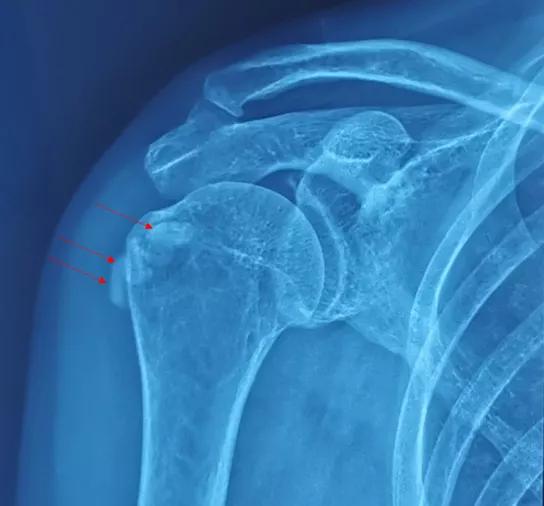

影像表现

钙化性肌腱炎依据X线检查即可明确诊断。所以大家没必要找关系,排长队去做核磁共振检查。